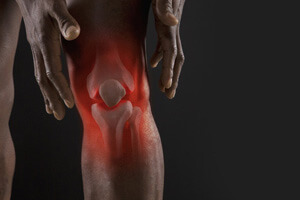

İnsanlar yürüme yeteneklerini yeniden kazandılar

Eklem ve omurga ağrısına elveda deyin!

Türk bir profesör tarafından keşfedilen ve eklem ağrısını

hemen ortadan kaldıran devrim niteliğindeki tedavi, 28 gün içinde% 100 sağlıklı eklemler ve omurga

sağlar